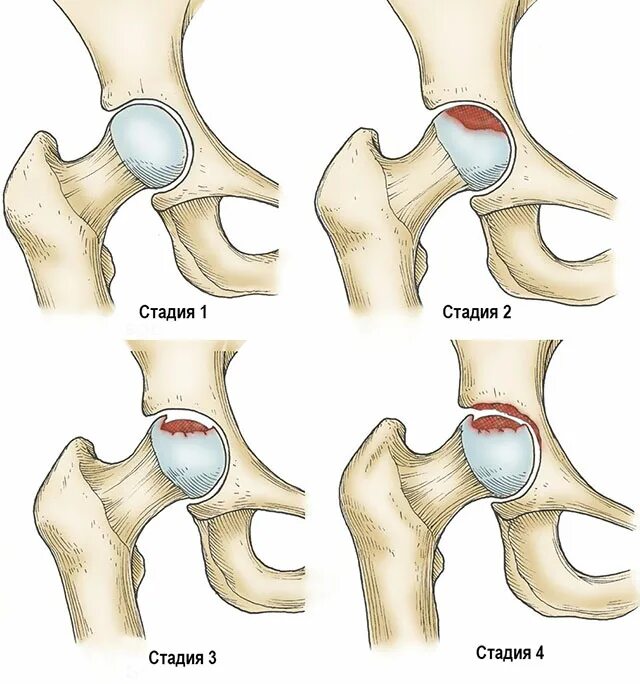

Склероз вертлужной впадины